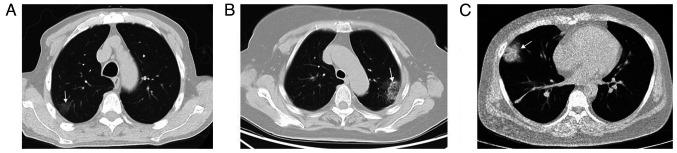

The object of the study was to evaluate comprehensively the value of chest non-contrasted CT (NC-CT) in detecting acute pulmonary thromboembolism (APE). All patients were categorized into two groups: i) With APE; and ii) without APE based on clinical diagnosis. Using the clot distribution on computed tomography pulmonary angiography (CTPA), APE was divided into central and peripheral APE. Imaging features including hyperdense lumen sign and peripheral wedge-shaped opacity on chest NC-CT were evaluated. The attenuation value of peripheral wedge-shaped opacity on NC-CT was compared between patients with and without APE. Among the 273 patients, there were 110 patients with APE, 49 patients with central APE and 61 patients with peripheral APE and 163 patients without APE. The hyperdense lumen sign had a sensitivity of 30.0% and a specificity of 97.6% in detecting APE. The sensitivity and specificity of hyperdense lumen sign in detecting central APE were 57.1 and 97.6%, respectively, while the relevant percentages in detecting peripheral APE were 8.2 and 97.6%, respectively. The mean attenuation value of peripheral wedge-shaped opacity in patients with APE was significantly lower than that in patients without APE (P<0.001). Regarding the age-adjusted D-dimer, there was a decrease of eight D-dimer positive cases for patients >50 years old without APE, confirmed by CTPA. In conclusion, chest NC-CT cannot be used as an alternative modality for CTPA in diagnosing APE, however, the hyperdense lumen sign had high specificity in the diagnosis of central APE. Patients with this symptom and increased D-dimer may not require further CTPA. The lower attenuation value of peripheral wedge-shaped opacity on NC-CT suggested APE, and CTPA confirmation was required. The age-adjusted D-dimer had higher specificity in excluding APE.

本研究的目的是全面评估胸部平扫CT(NC-CT)在检测急性肺血栓栓塞症(APE)中的价值。所有患者根据临床诊断分为两组:i)患有APE;ii)未患有APE。根据计算机断层扫描肺动脉造影(CTPA)上的血栓分布,APE分为中央型和外周型APE。评估胸部NC-CT上的高密度管腔征和外周楔形实变影等影像特征。比较有和无APE患者NC-CT上外周楔形实变影的衰减值。273例患者中,有110例患有APE,其中49例为中央型APE,61例为外周型APE,163例未患有APE。高密度管腔征检测APE的灵敏度为30.0%,特异度为97.6%。高密度管腔征检测中央型APE的灵敏度和特异度分别为57.1%和97.6%,而检测外周型APE的相应百分比分别为8.2%和97.6%。APE患者外周楔形实变影的平均衰减值显著低于无APE患者(P<0.001)。关于年龄校正的D-二聚体,经CTPA证实,>50岁无APE患者的D-二聚体阳性病例减少了8例。总之,胸部NC-CT不能作为CTPA诊断APE的替代方法,然而,高密度管腔征在中央型APE诊断中具有高特异度。有此症状且D-二聚体升高的患者可能无需进一步行CTPA检查。NC-CT上外周楔形实变影衰减值较低提示APE,需CTPA确诊。年龄校正的D-二聚体在排除APE方面具有更高的特异度。